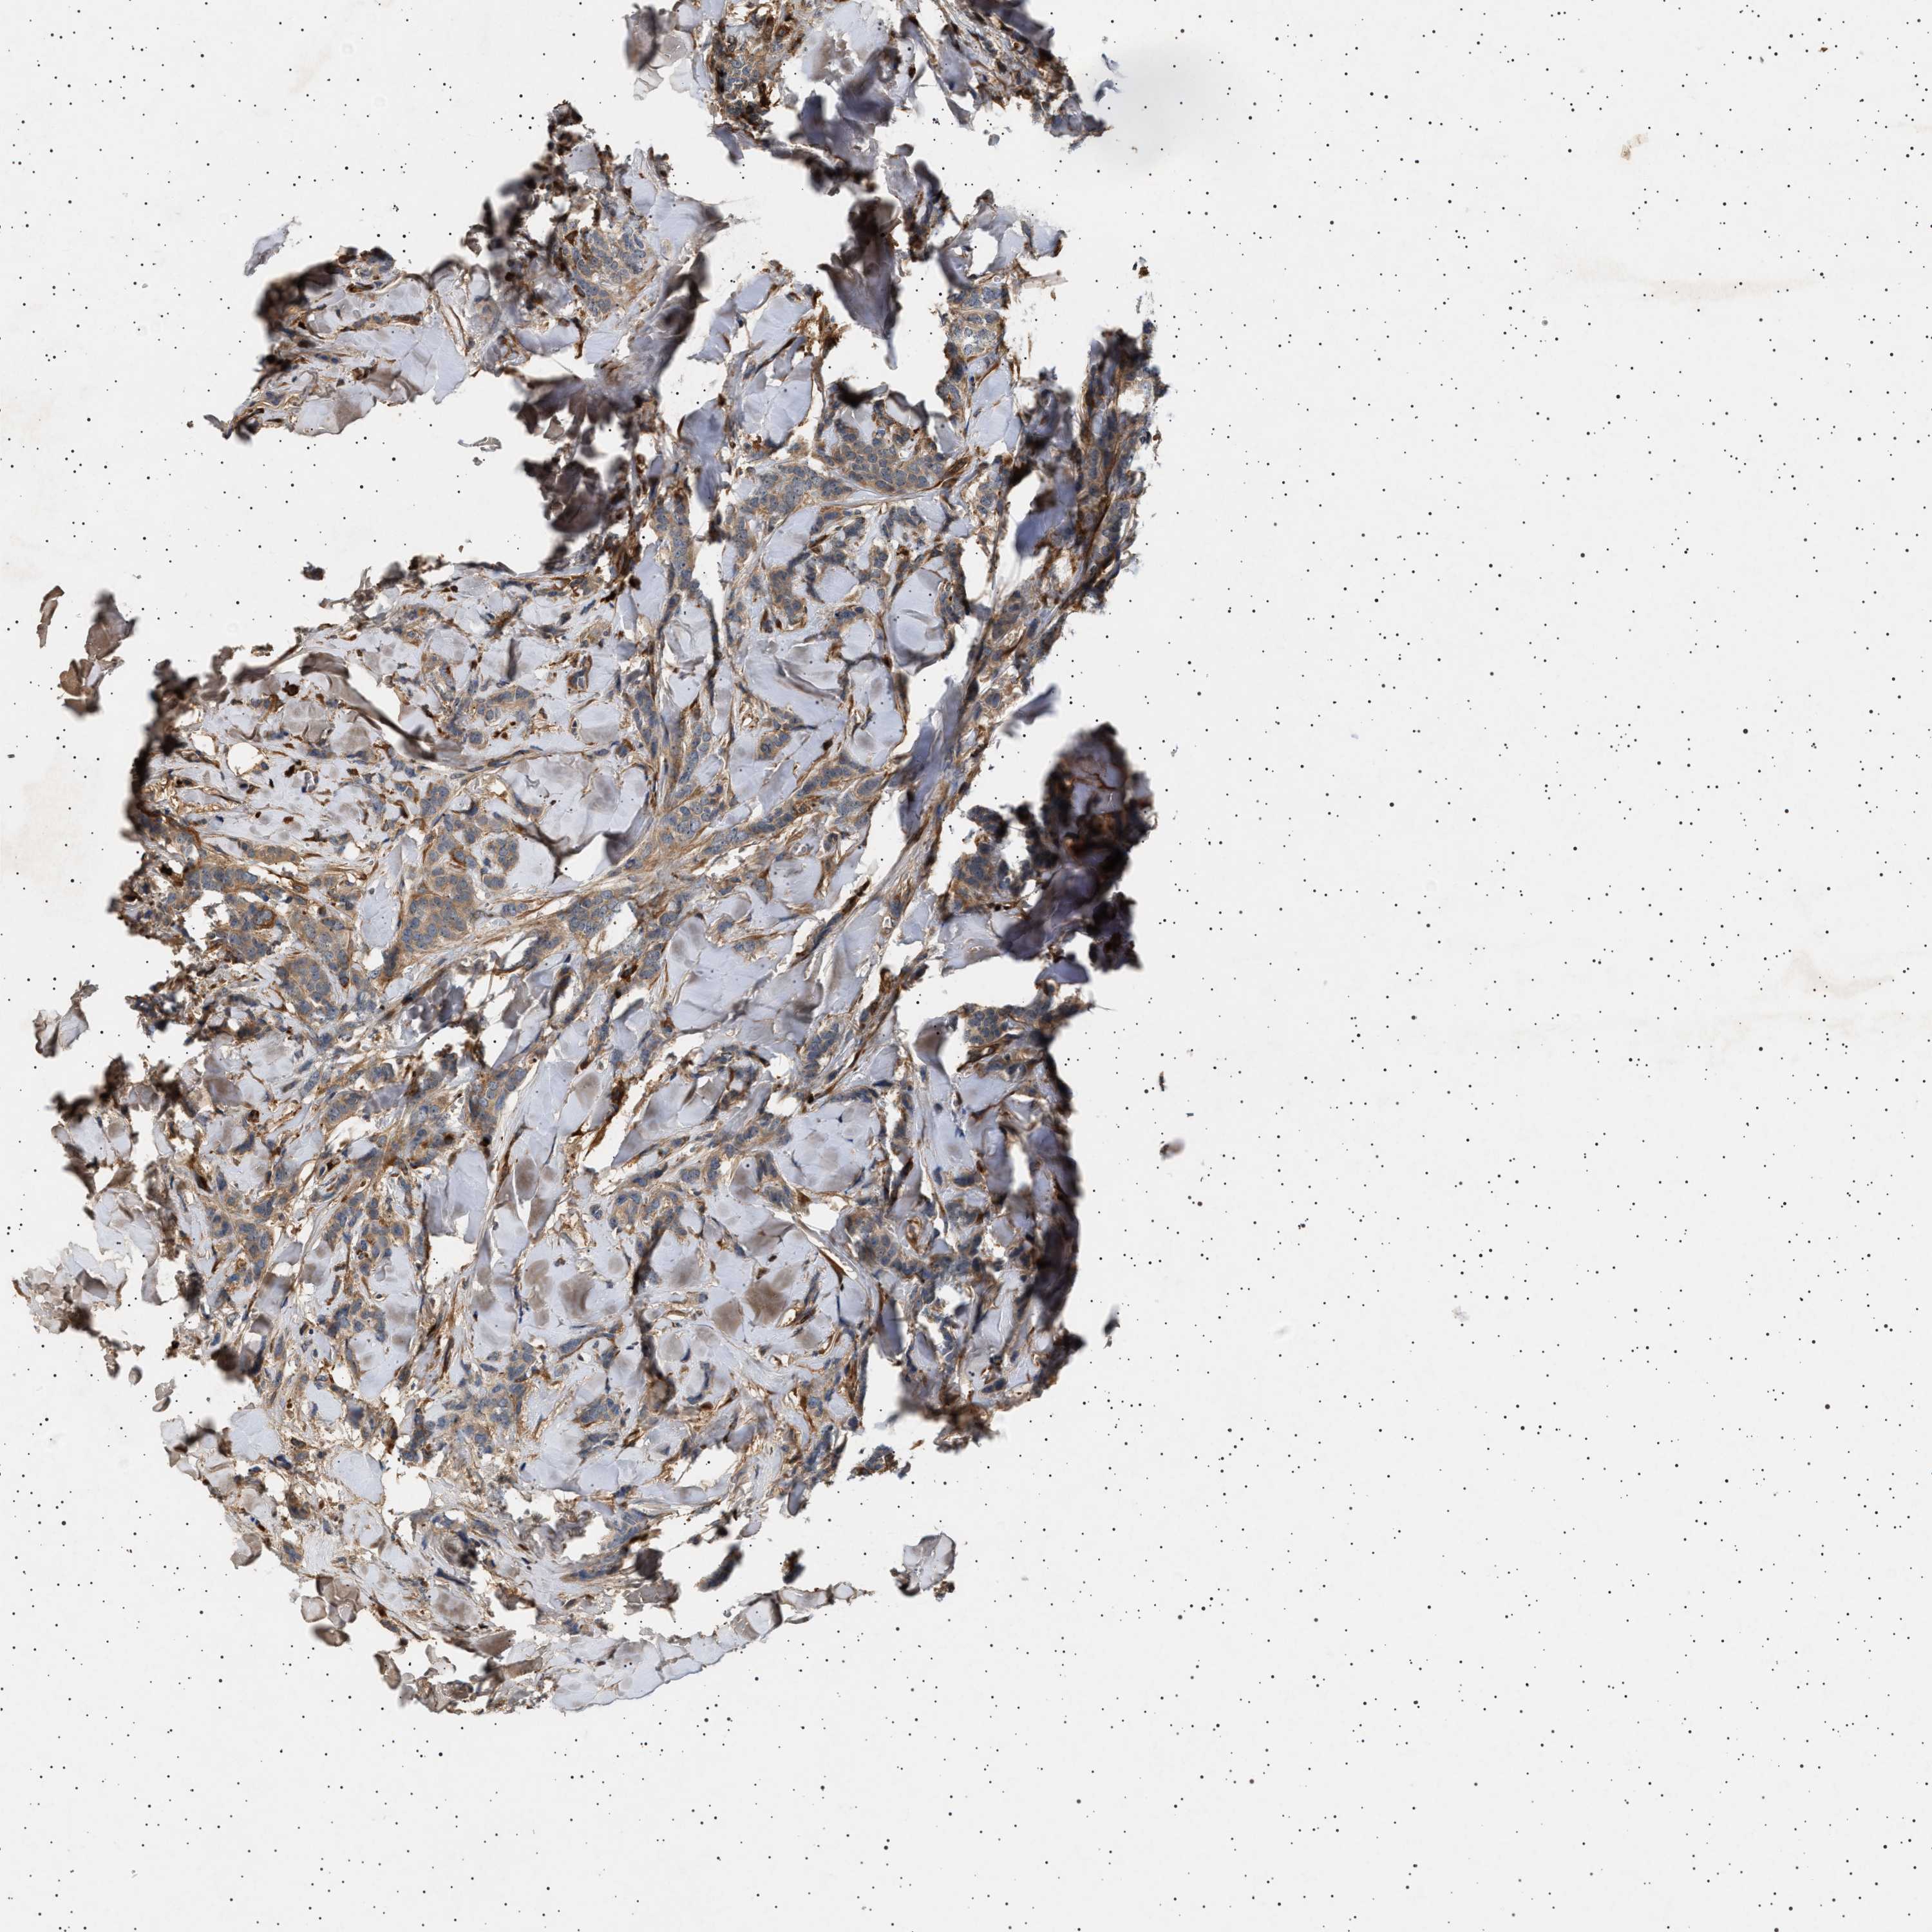

CANCER BREAST CANCER Show tissue menu

BRCA TCGA BRCA VALIDATION PROTEIN EXPRESSION